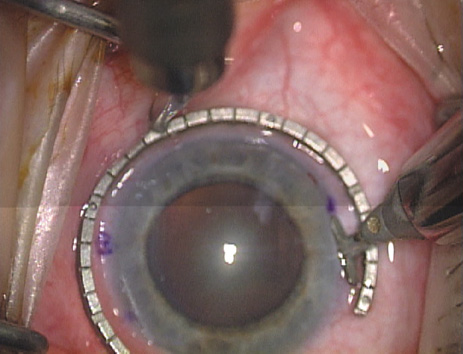

Case 2 is a 79-year-old woman who presented with a very dense left cataract. Her refraction was recorded at −2.25 +2.75 × 125 with a difficult end point. Her manual keratometry and topography measurements were consistent and revealed slightly less than 1.75 D at 120 degrees. Because of the questionable refraction, greater value was placed on the corneal measurements. Based upon the cataract nomogram, the plan was for paired LRIs of 40 degrees to be placed over the steep 120-degree axis (Figs. 1219).

Fig. 12. In this left eye, the steep meridian is at the 120-degree axis and has been delineated by opposing limbal marks. The upper left hand ink mark represents the 6:00 position for orientation. (Reprinted from Hardten DR, Lindstrom RL, Davis EA. Phakic Intraocular Lenses: Principles and Practice. Thorofare, NJ: SLACK Incorporated, 2004, with permission.)